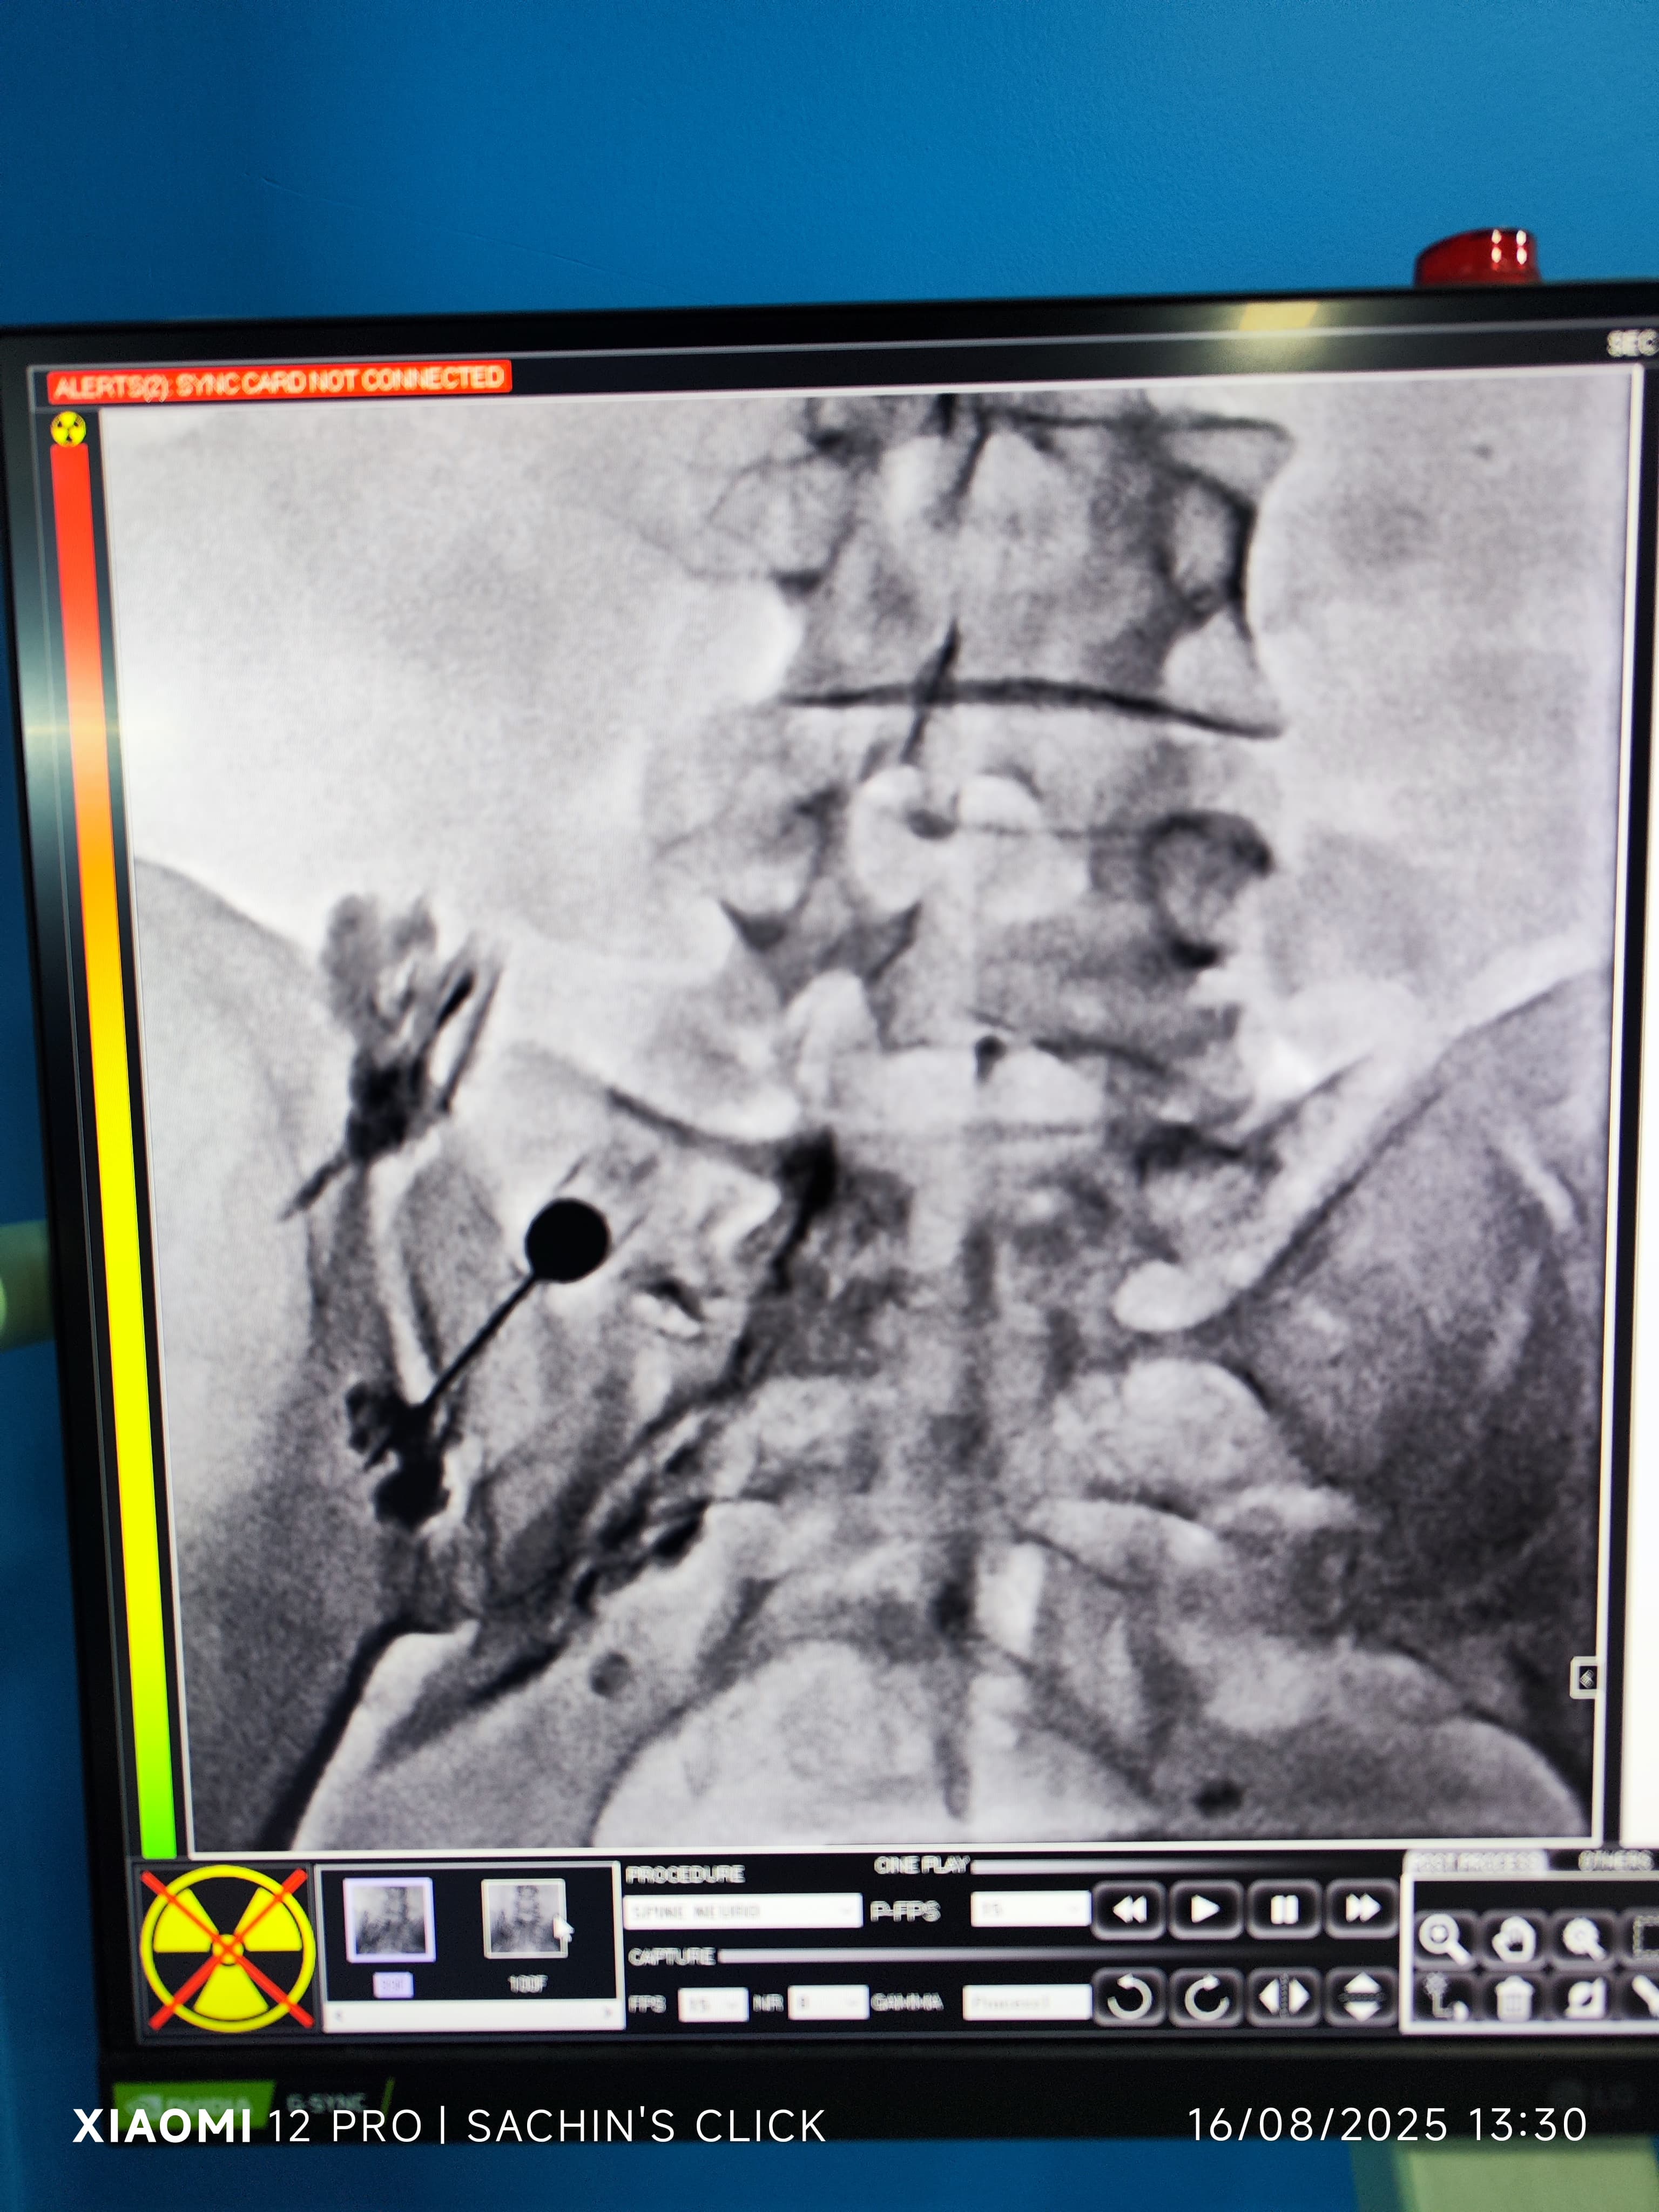

Glimpses of Advance Pain Care

Step inside our clinic and see our commitment to a healing environment and advanced care.